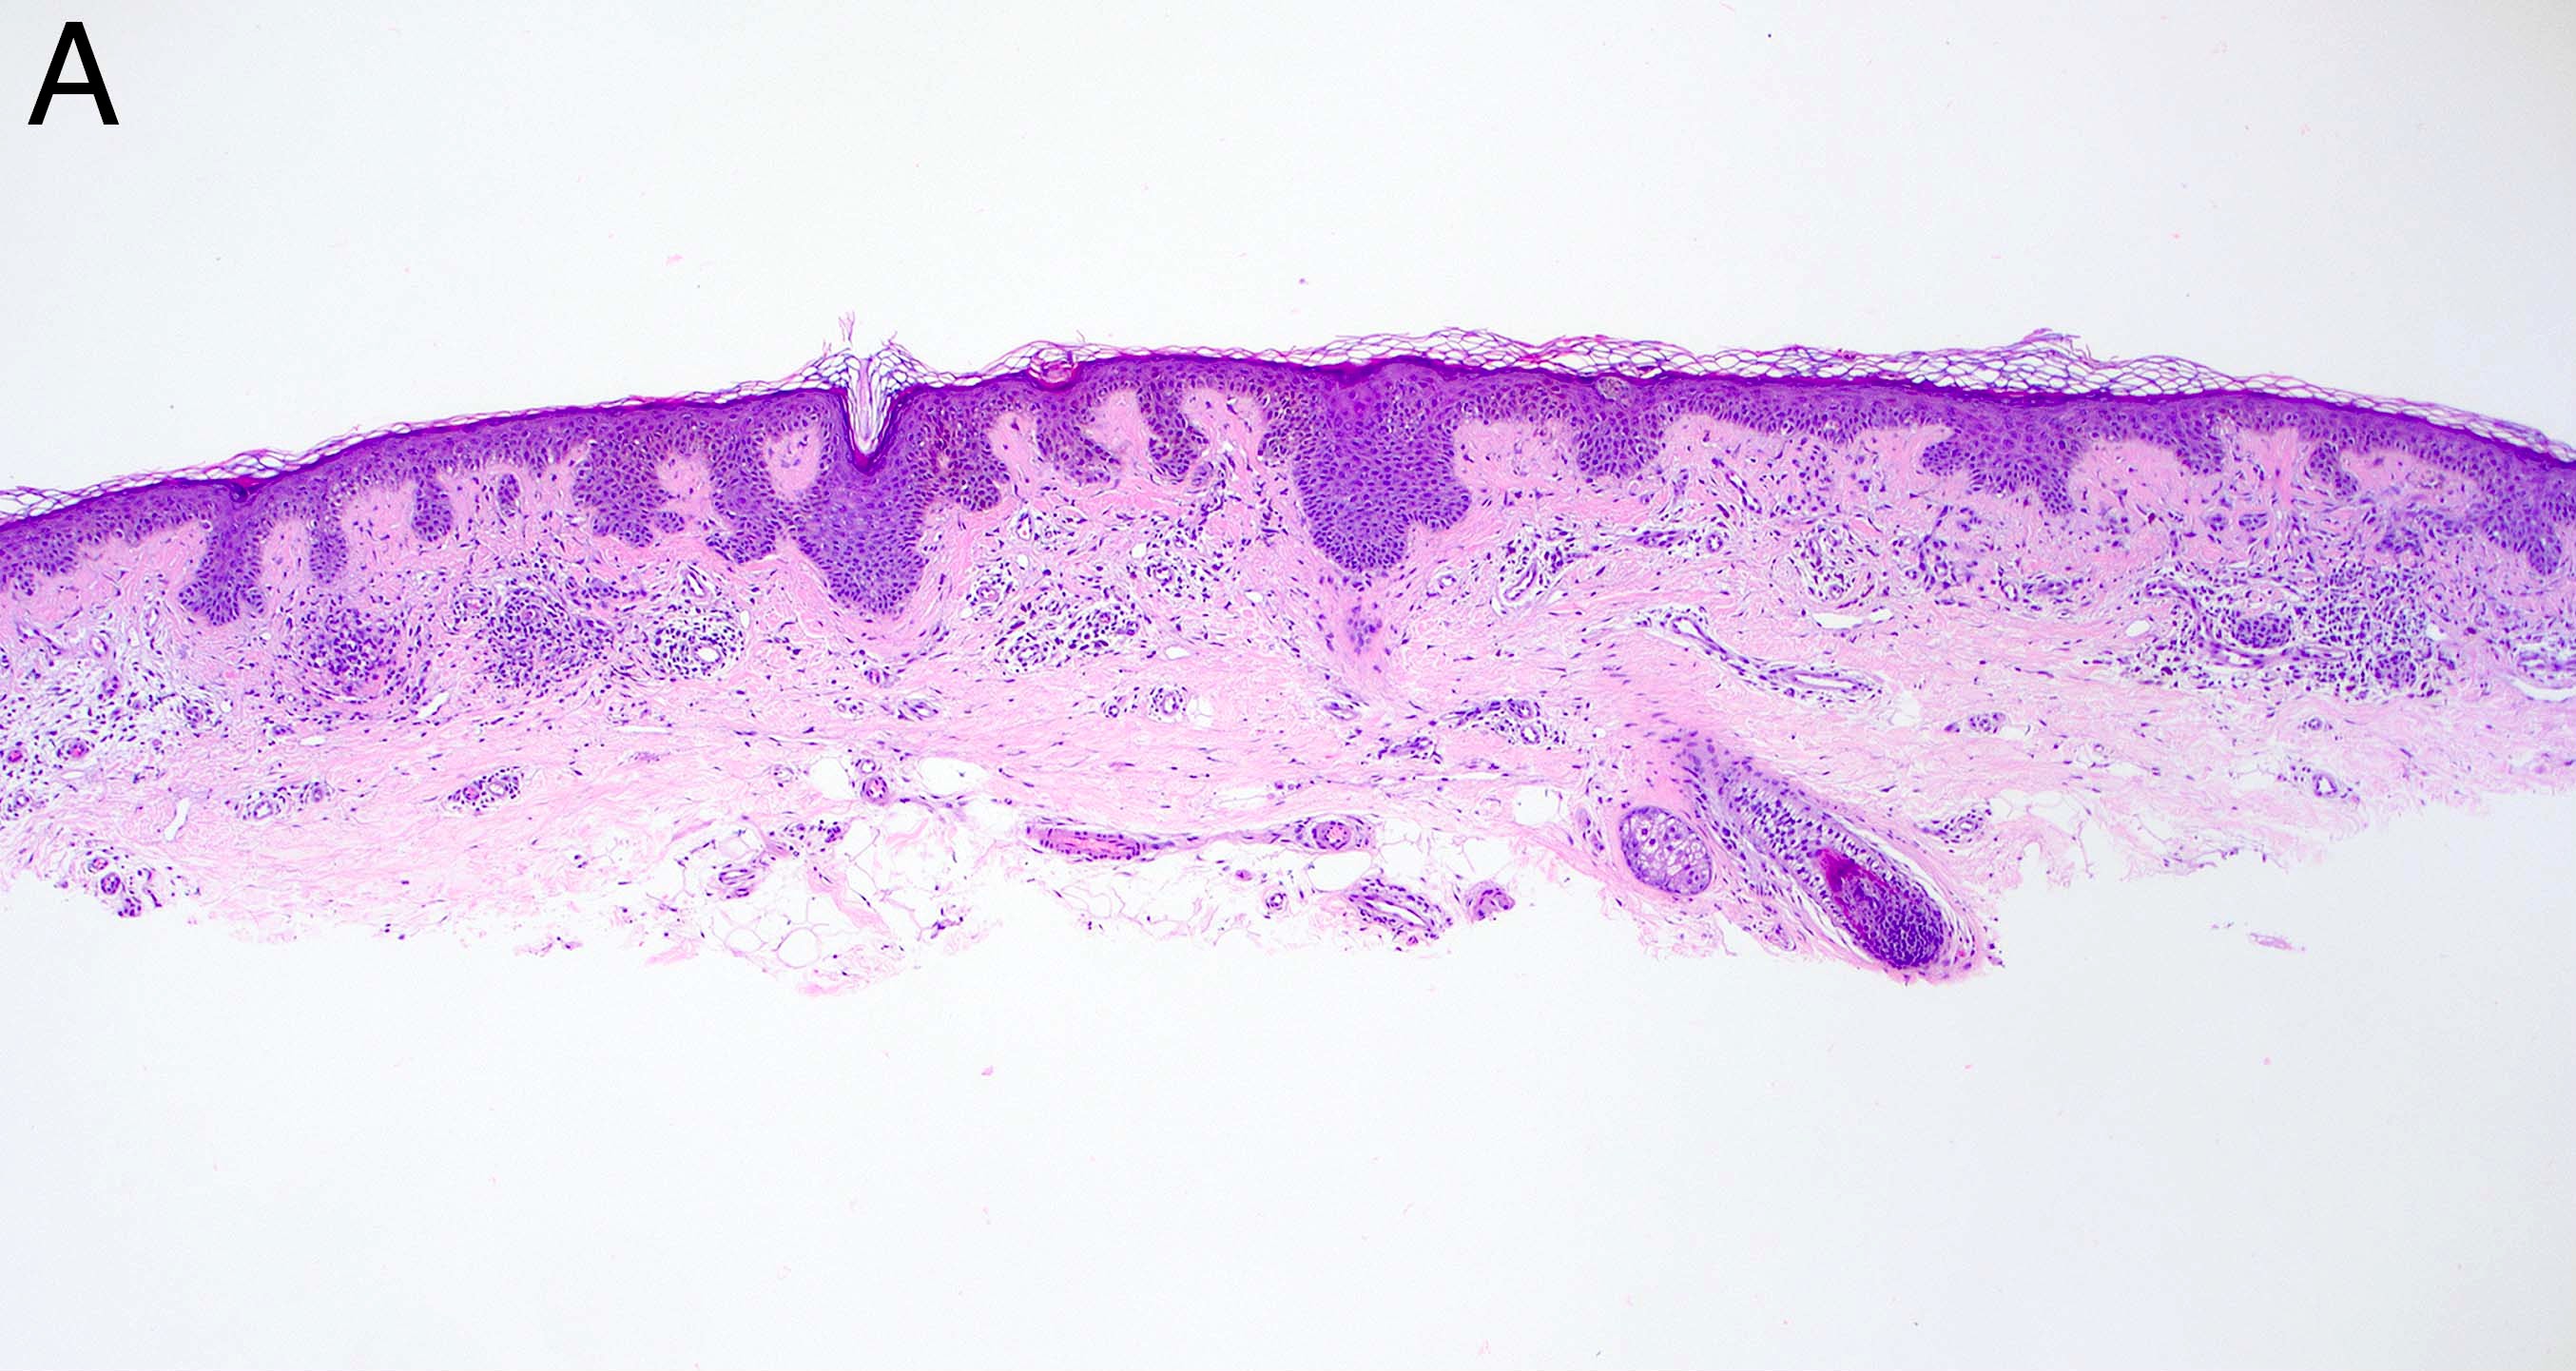

- Melanocytic nevi of the breast (Am J Dermatopathol 2016;38:867):

- May contain large irregular dyshesive nests in close proximity to one another

- Junctional nests may not be centered and can be placed within inter-rete spaces and along sides of rete

- Nests may have variable pigmentation (results in globules seen on dermoscopic exam)

- Nests may have prominent horizontal streaming resulting in rete blunting or epidermal effacement

- Cytologic atypia is common

- Maturation with melanocyte descent should be retained